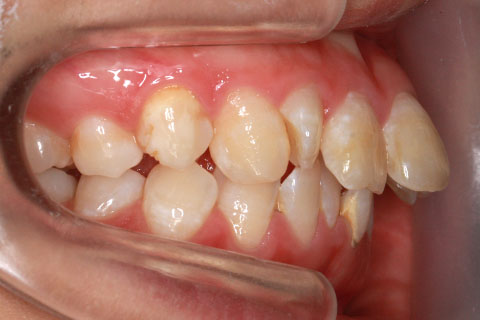

矯正期間24ヶ月

ハーフリンガル矯正4(上の歯のみ舌側矯正で治療)

治療前

治療中

治療後

- 年齢・性別

- 23歳女性

- 治療期間

- 2年0ヶ月

- 抜歯

- 上下4番抜歯

- 治療費

- 110万円

- 備考

- マルチブラケットを用いた矯正治療

- 治療内容

- 施術の副作用(リスク)

- 表側矯正と比較して、前歯のラビッティング(舌側傾斜)を起こしやすい。